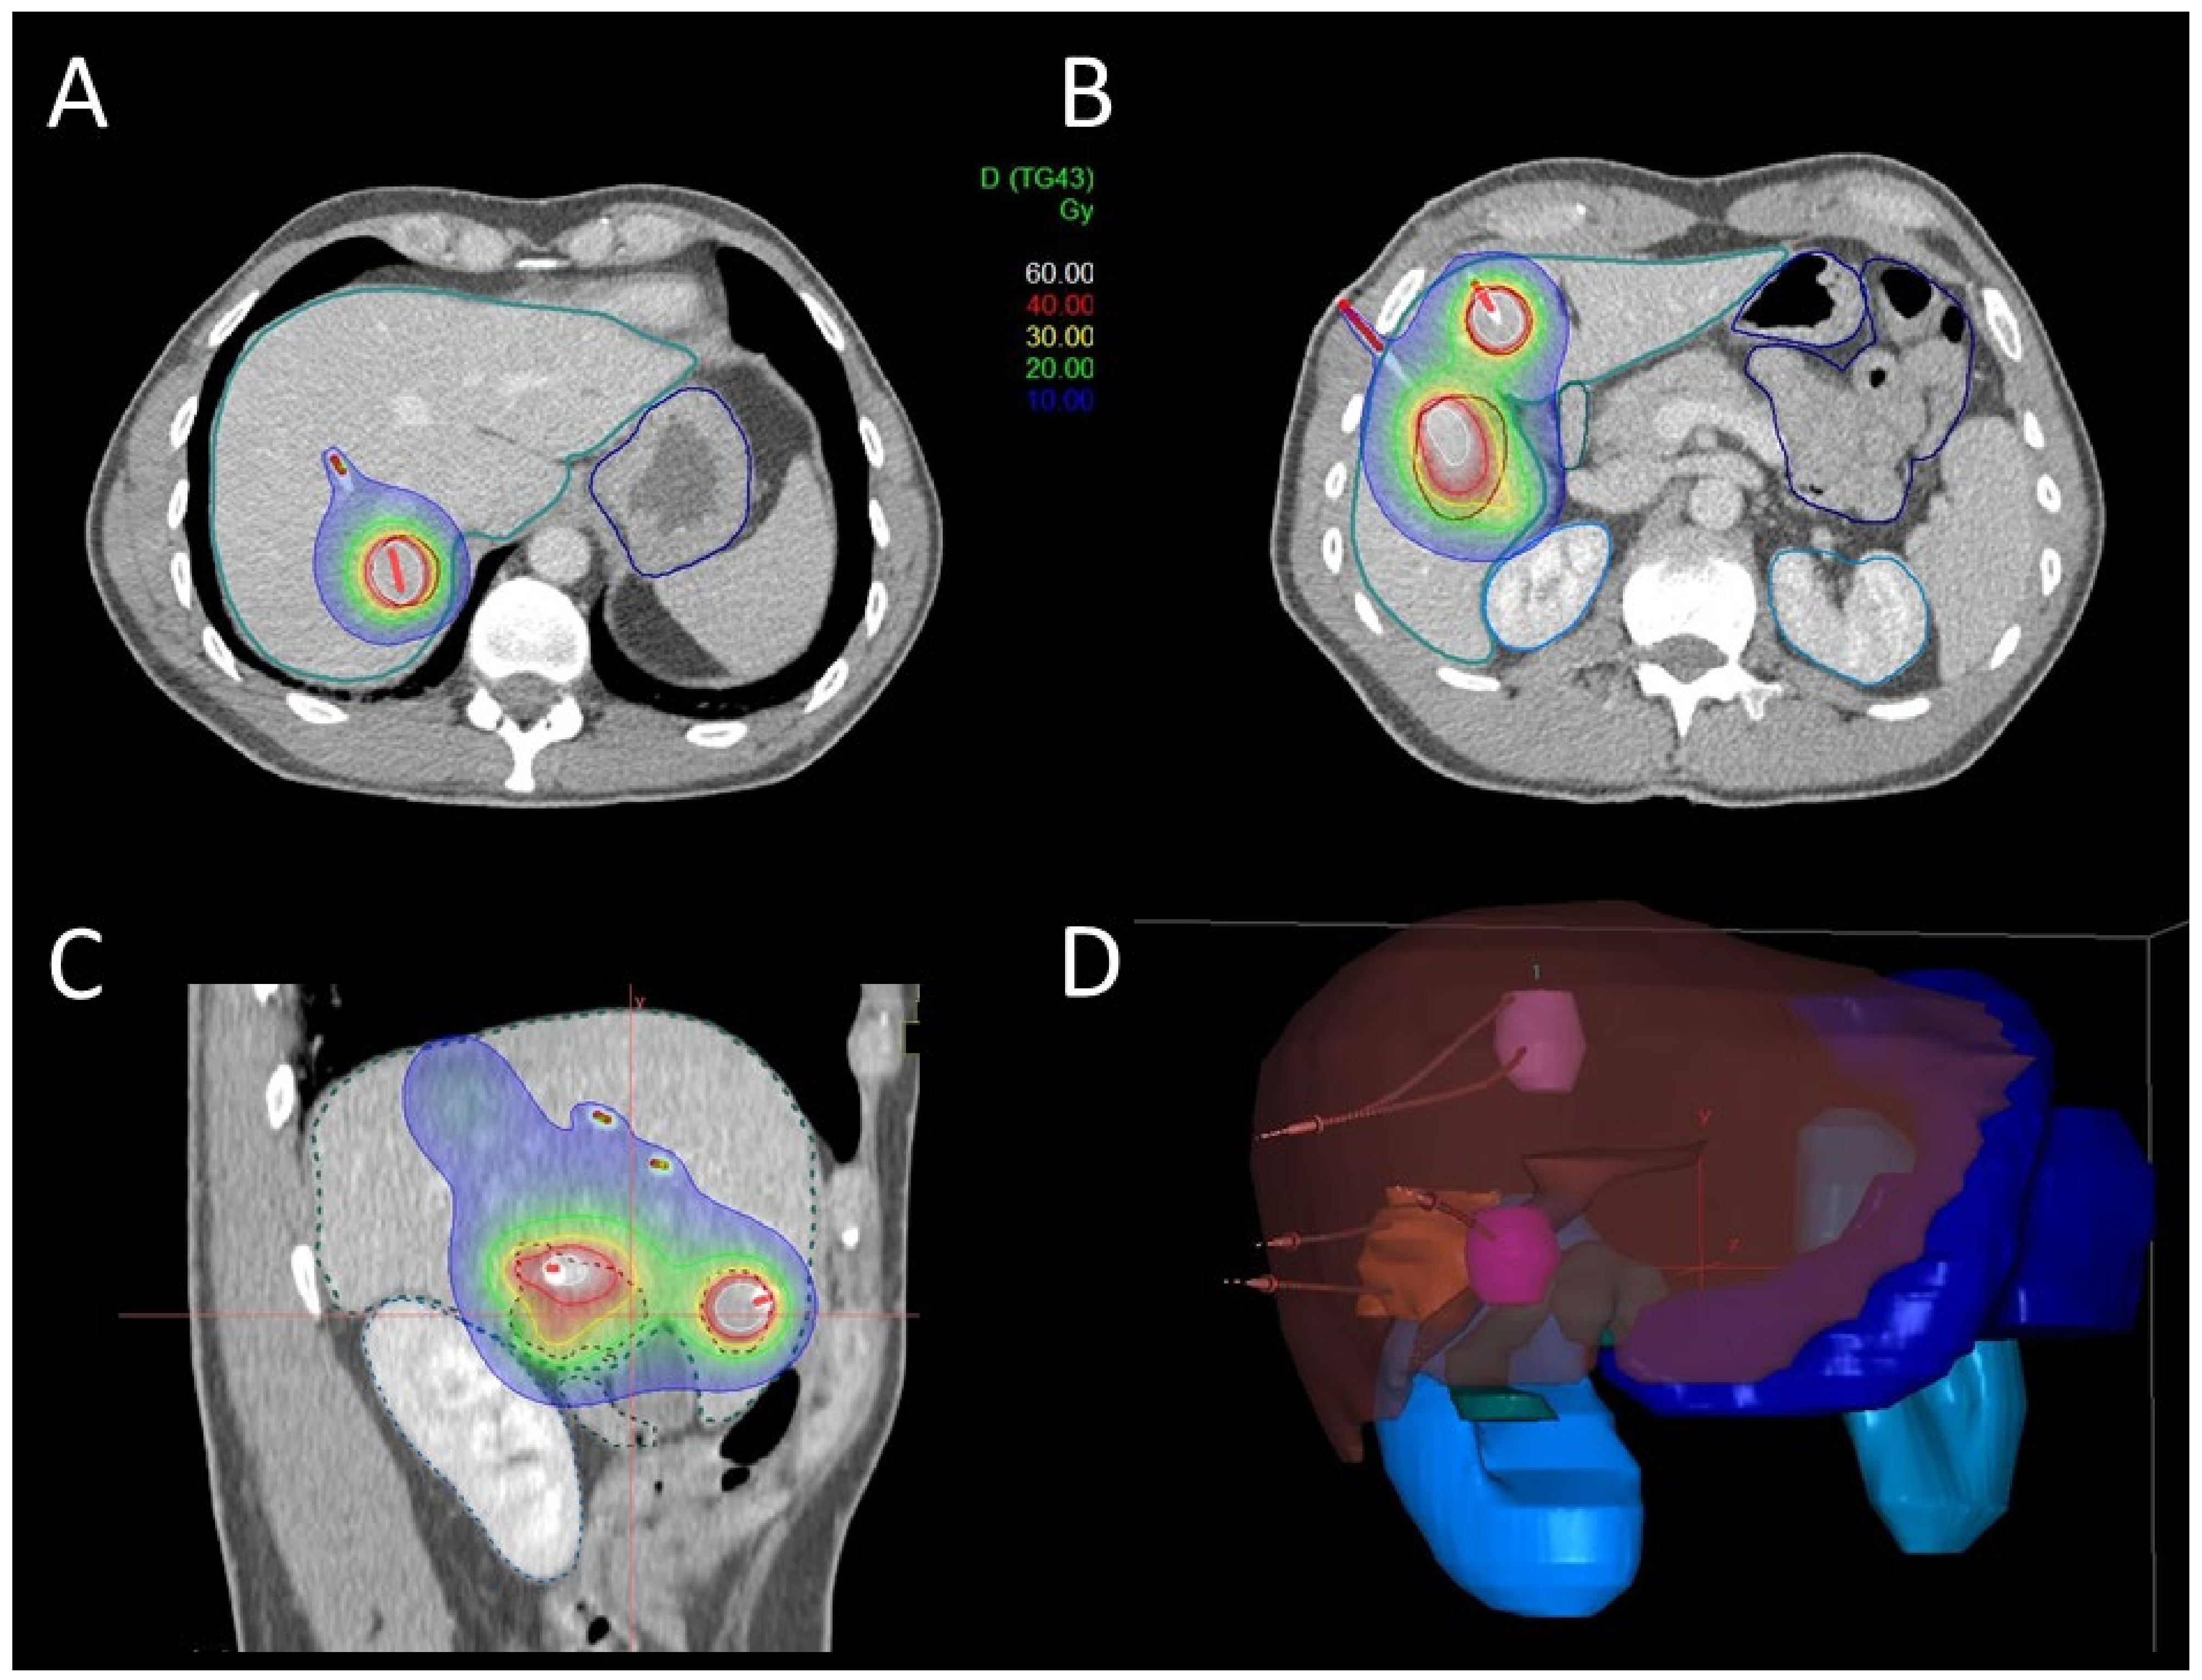

2.2. Brachytherapy